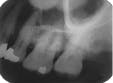

The bisecting-angle technique creates specific errors in vertical angulation, giving shortened images (see Radiograph 2 as an example of foreshortening) or lengthened images (see Radiograph 3 as an example of elongation). Substantially shortened images occur because there is too much vertical angulation. This causes distortion in the reproduction of the actual size of the tooth. The solution requires a decrease of the vertical angulation by at least 10 degrees.

Conversely, lengthened im-ages occur because there is not enough vertical angulation. Another reason is that the film is curved in the mouth. Increasing the vertical angulation by at least 10 degrees and repositioning the film to prevent bending will alleviate this distorted image.